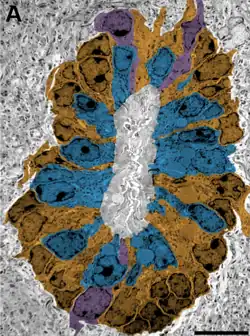

Ocupa el centro de la médula espinal, ubicándose en el centro de la comisura gris dividiéndola en una comisura gris anterior y en una comisura gris posterior.

En su trayecto su forma varía: es oval en la médula cervical, esférico en la médula torácica y triangular o en forma de T en la médula lumbar. Esta estructura representa un vestigio del desarrollo embrionario del tubo neural.[3]

Su superficie interior en contacto con el líquido cefalorraquídeo, está tapizada por células de estirpe glial llamadas células ependimarias.